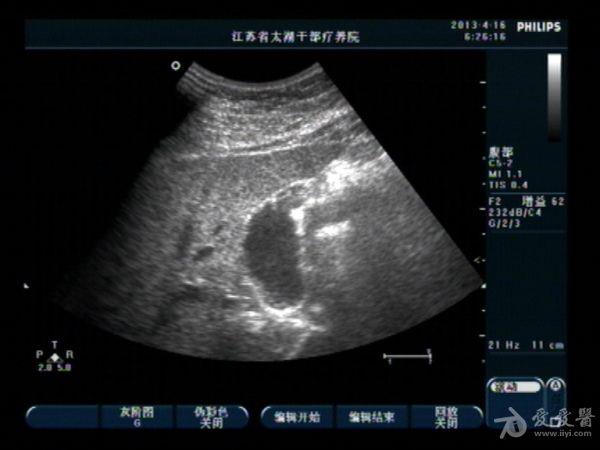

胆囊底部稍低回声区,胆泥沉积?胆囊癌不像吧?,请分析

男性,40,无右上腹痛

变换**,轻轻地敲打胆囊区,如果是胆泥块,会被敲的松散